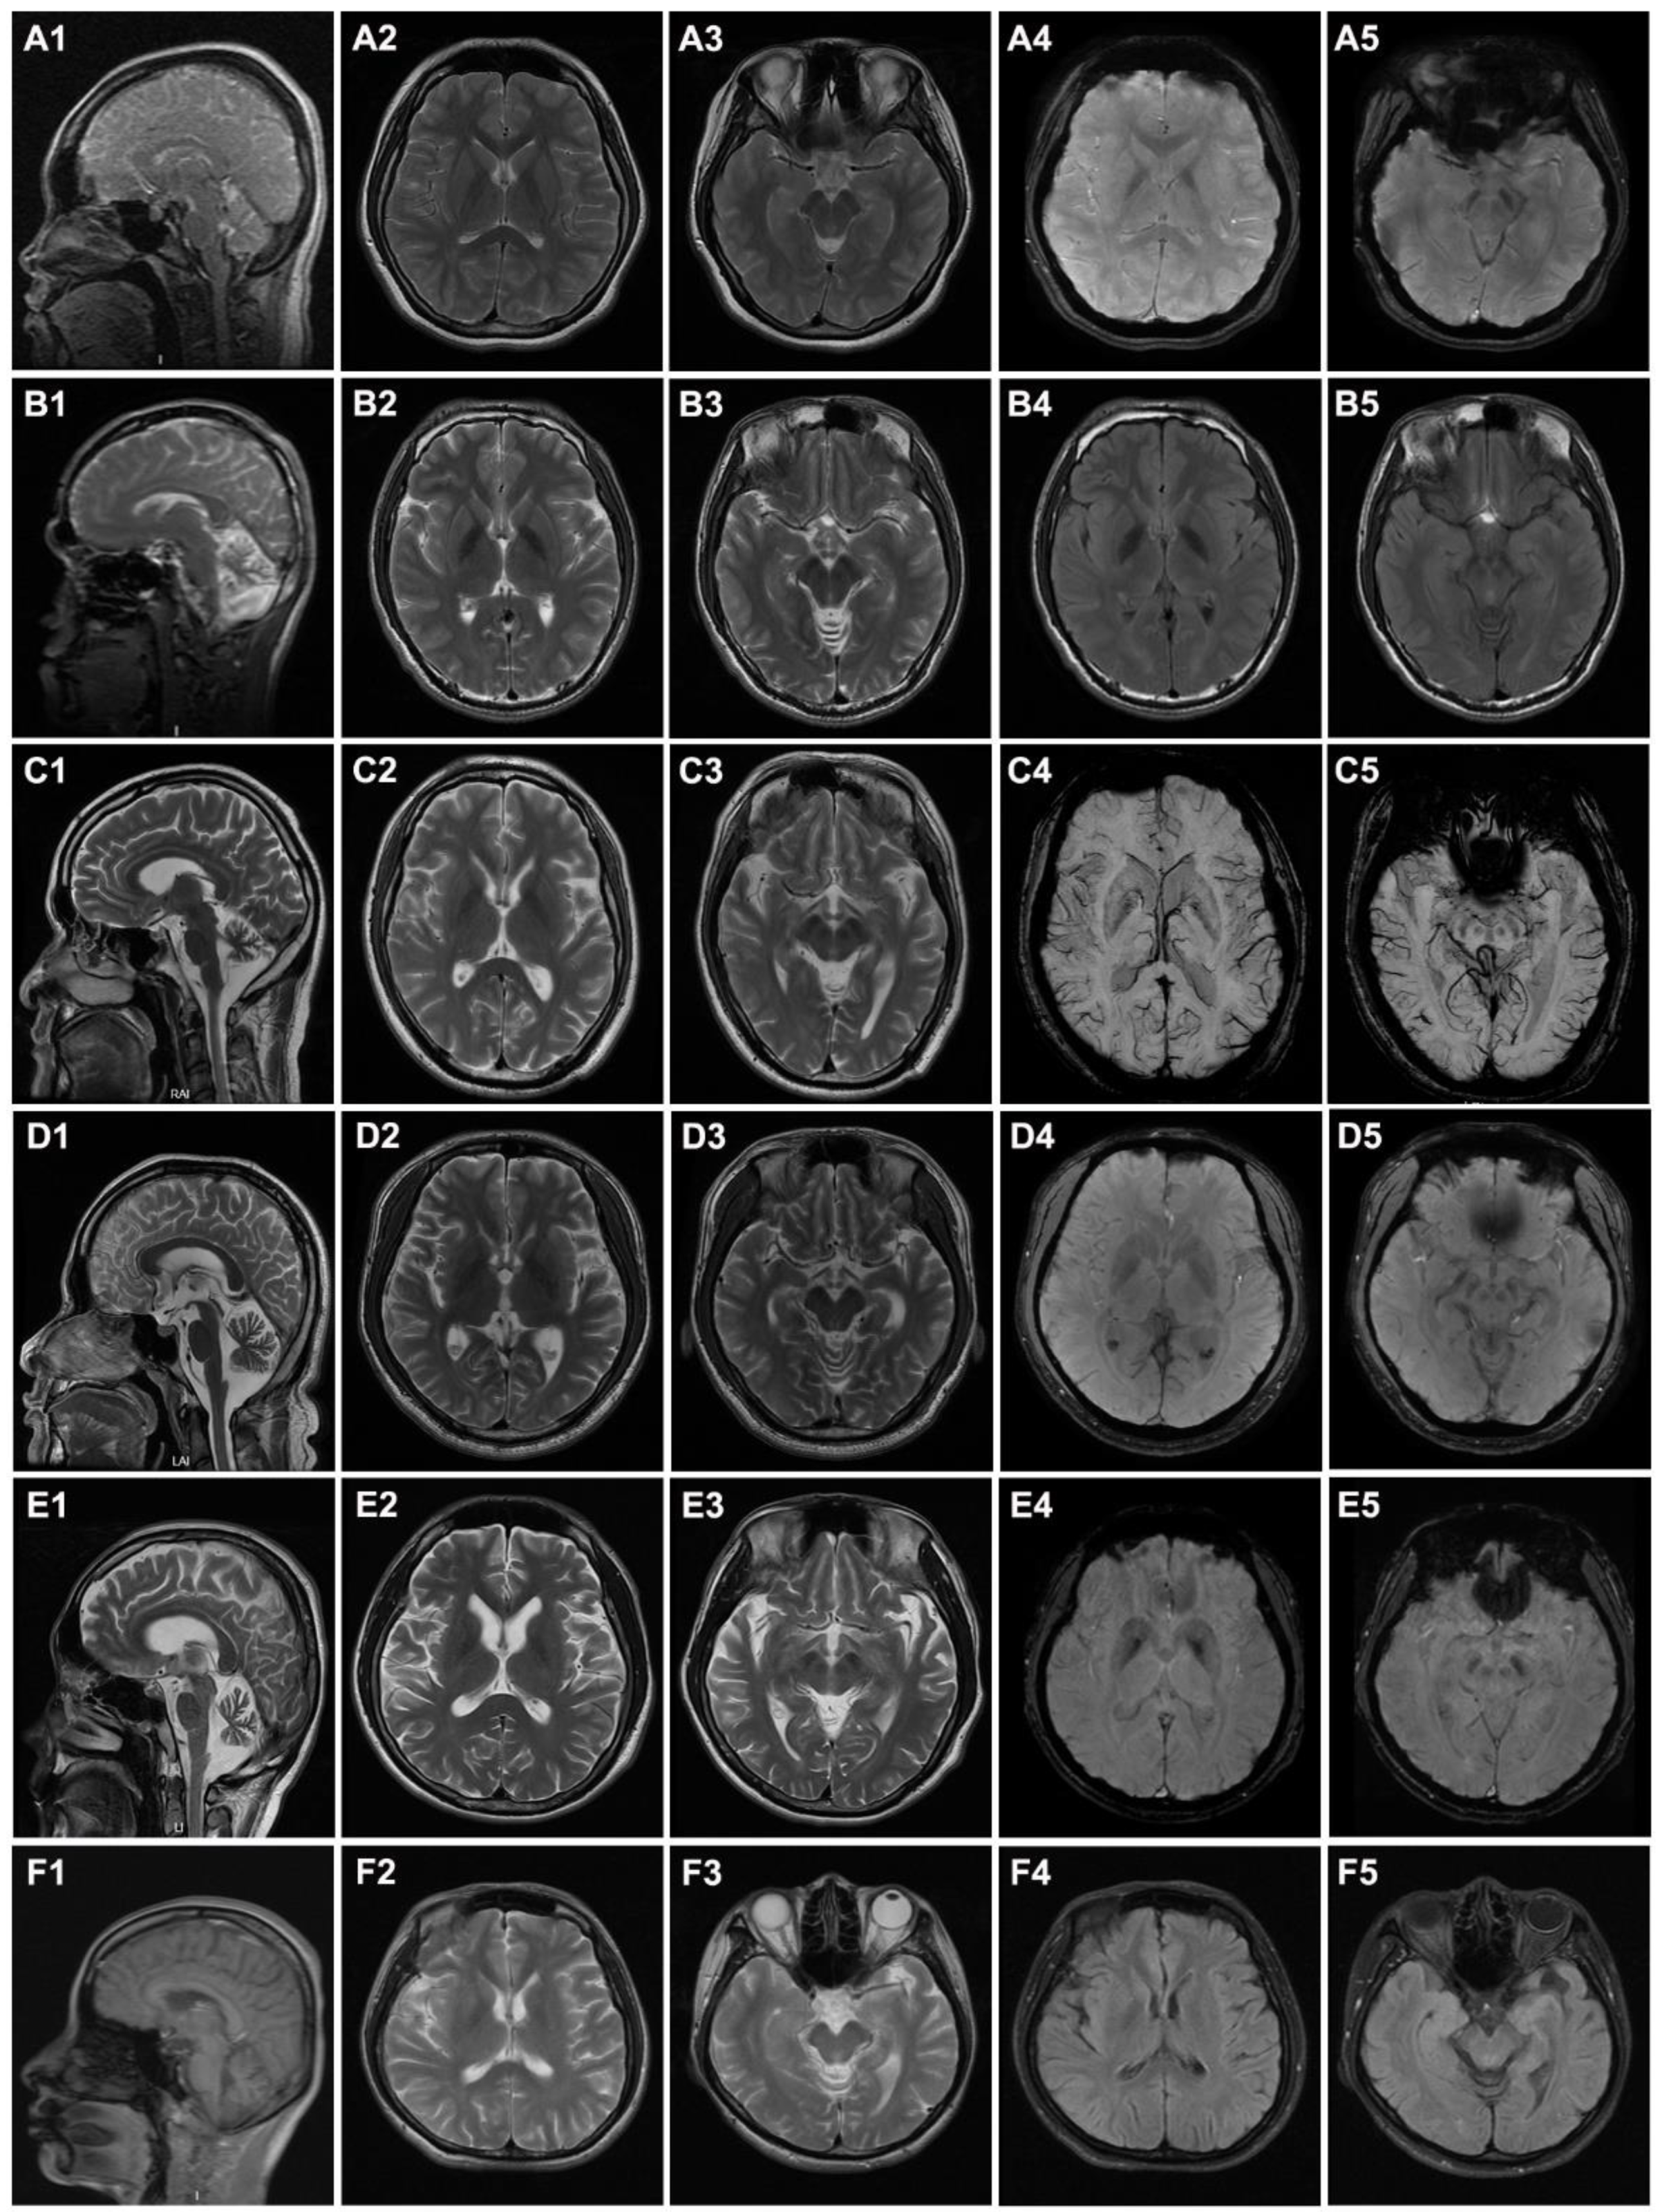

| Cerebellar atrophy | + | + | + | + | + | + |

| Cerebral atrophy | − | − | + | − | + | + |

| Iron deposition in globus pallidus | + | + | − | − | + | − |